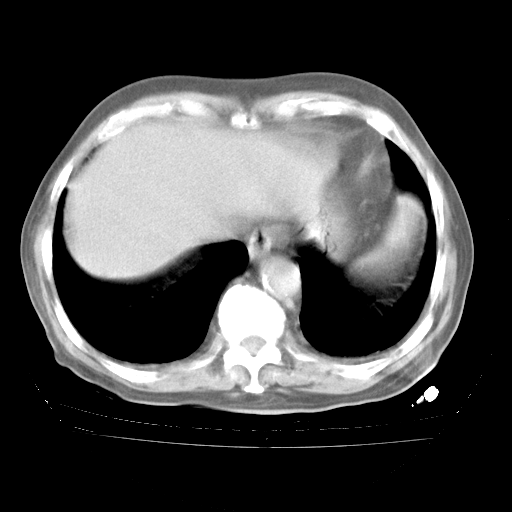

4月28日肺部CT——再次出现类似去年5月9日——透光度降低,“间质性”改变。